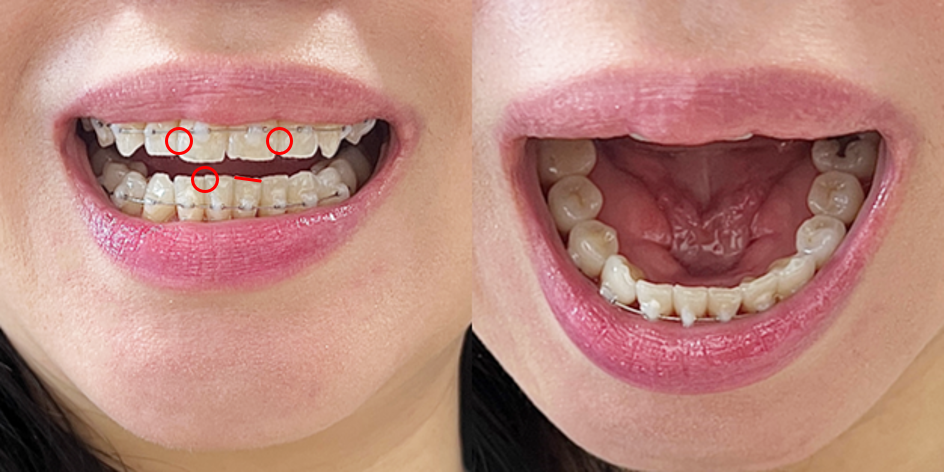

- 12월, 1월부터 앞니 교합이 안맞는거 같다고 말씀 드렸는데 계속 저렇게 어긋나 있습니다

- 앞니 왼쪽 라인은 들어가있고 오른쪽 라인은 나와있어서 고개를 들어서 앞니라인을 보면 라인이 불규칙합니다

- 앞니 이빨 선이 왼쪽으로 치우쳐 있고 이빨이 위로 뻗쳐보이는 느낌입니다.

- 송곳니 기준 4번째 치아가 비틀어져 있습니다 > 월치료때 말씀드리니 원래 치아가 이렇게 생긴거라고 하셨는데 이게 맞는건가요?

- 송곳니 기준 2, 3번 치아는 정면에서 봤을때 튀어나와 있는것처럼 보입니다 > 이또한 4번치아 때문에 그런진 모르겠지만 아랫니도 불규칙한것처럼 보입니다